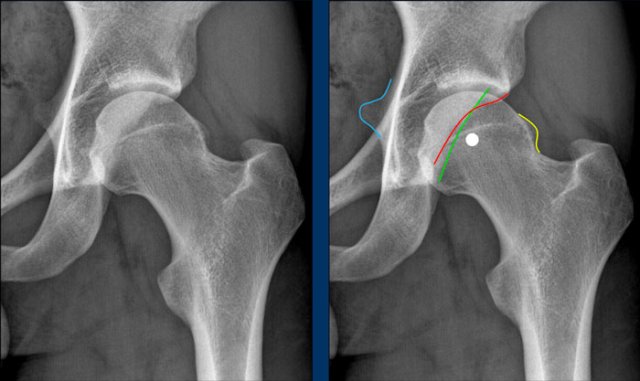

Normal anteversion of the acetabulum

This is a detail of the normal left hip on an AP Pelvis X-ray.

As a result of the normal anteverted orientation of the acetabulum, the border of the anterior wall (red line) projects medially to the posterior wall (green line) , i.e. no cross over.

The posterior wall projects laterally to the center of the femoral head, i.e. no posterior wall sign.

The ischial spine (blue line) does not project medially, i.e. no ischial spine sign.